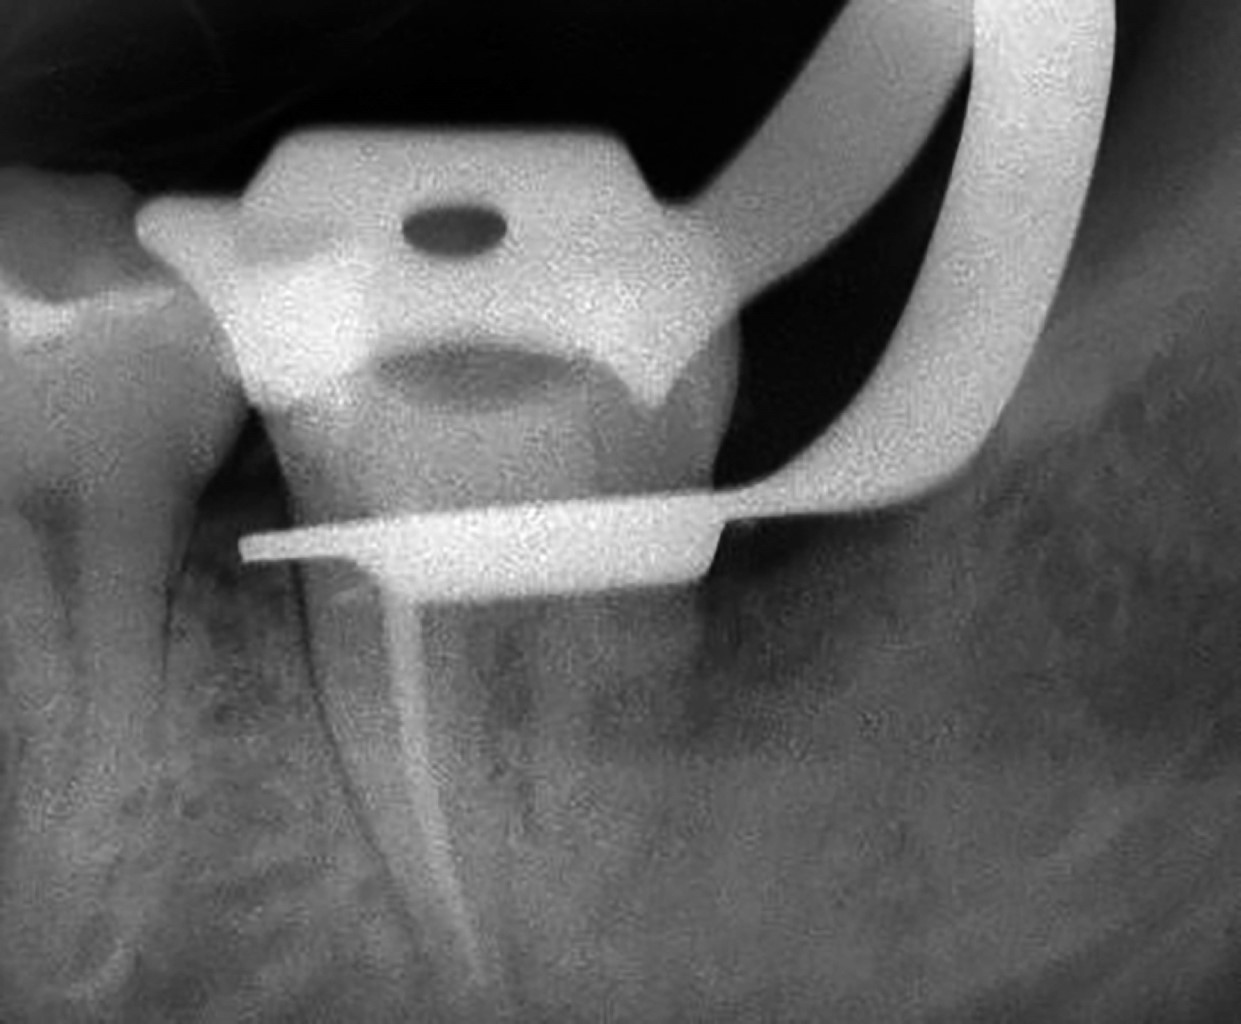

Se trata de un paciente masculino de 32 años, sin antecedentes médicos de importancia, que acude a consulta de una colega cirujano dentista de práctica general por presentar dolor moderado, constante y de 48 horas de evolución en zona de molares inferiores izquierdos, al hacer la exploración clínica y radiográfica, se detecta retención de tercer molar inferior, clasificándose como clase I C de Pell y Gregory y en una posición horizontal según la escala de Winter (Figura 1).10,11

La radiografía muestra una superposición de imágenes entre la corona del tercer molar retenido y la raíz distal del segundo molar, que no permite observar la raíz distal del segundo molar.

Figura 1

Figura 2